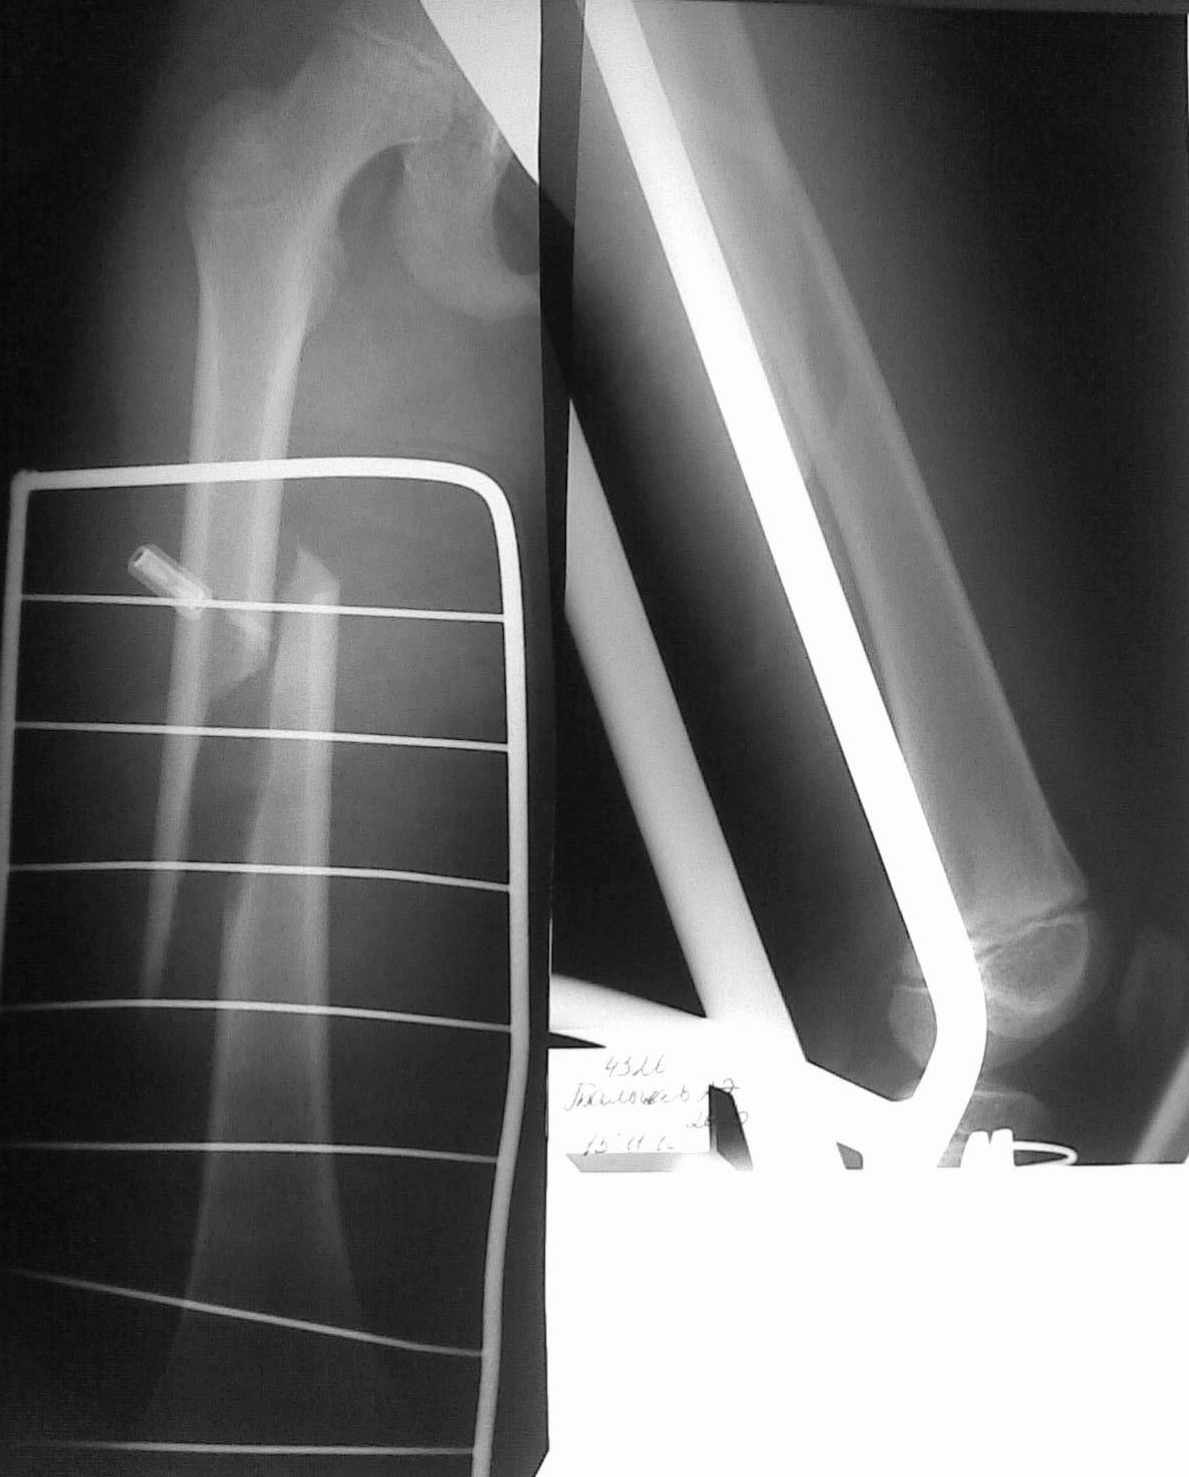

Уважаемые коллеги! В связи с малым опытом лечения переломов трубчатых костей у детей. хотелось бы узнать Ваше мнение о методах остеосинтеза данного пациента.

Ребенок 10 лет, травма спортивная. есть проблемы с "железом". думаем о интрамедулярном остеосинтезе + толстый кетгут.